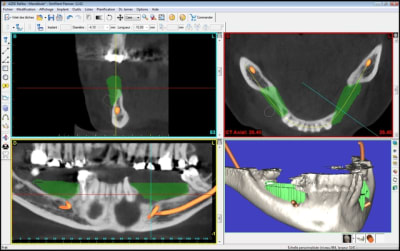

simulation_greffe_iwz2t7.jpg